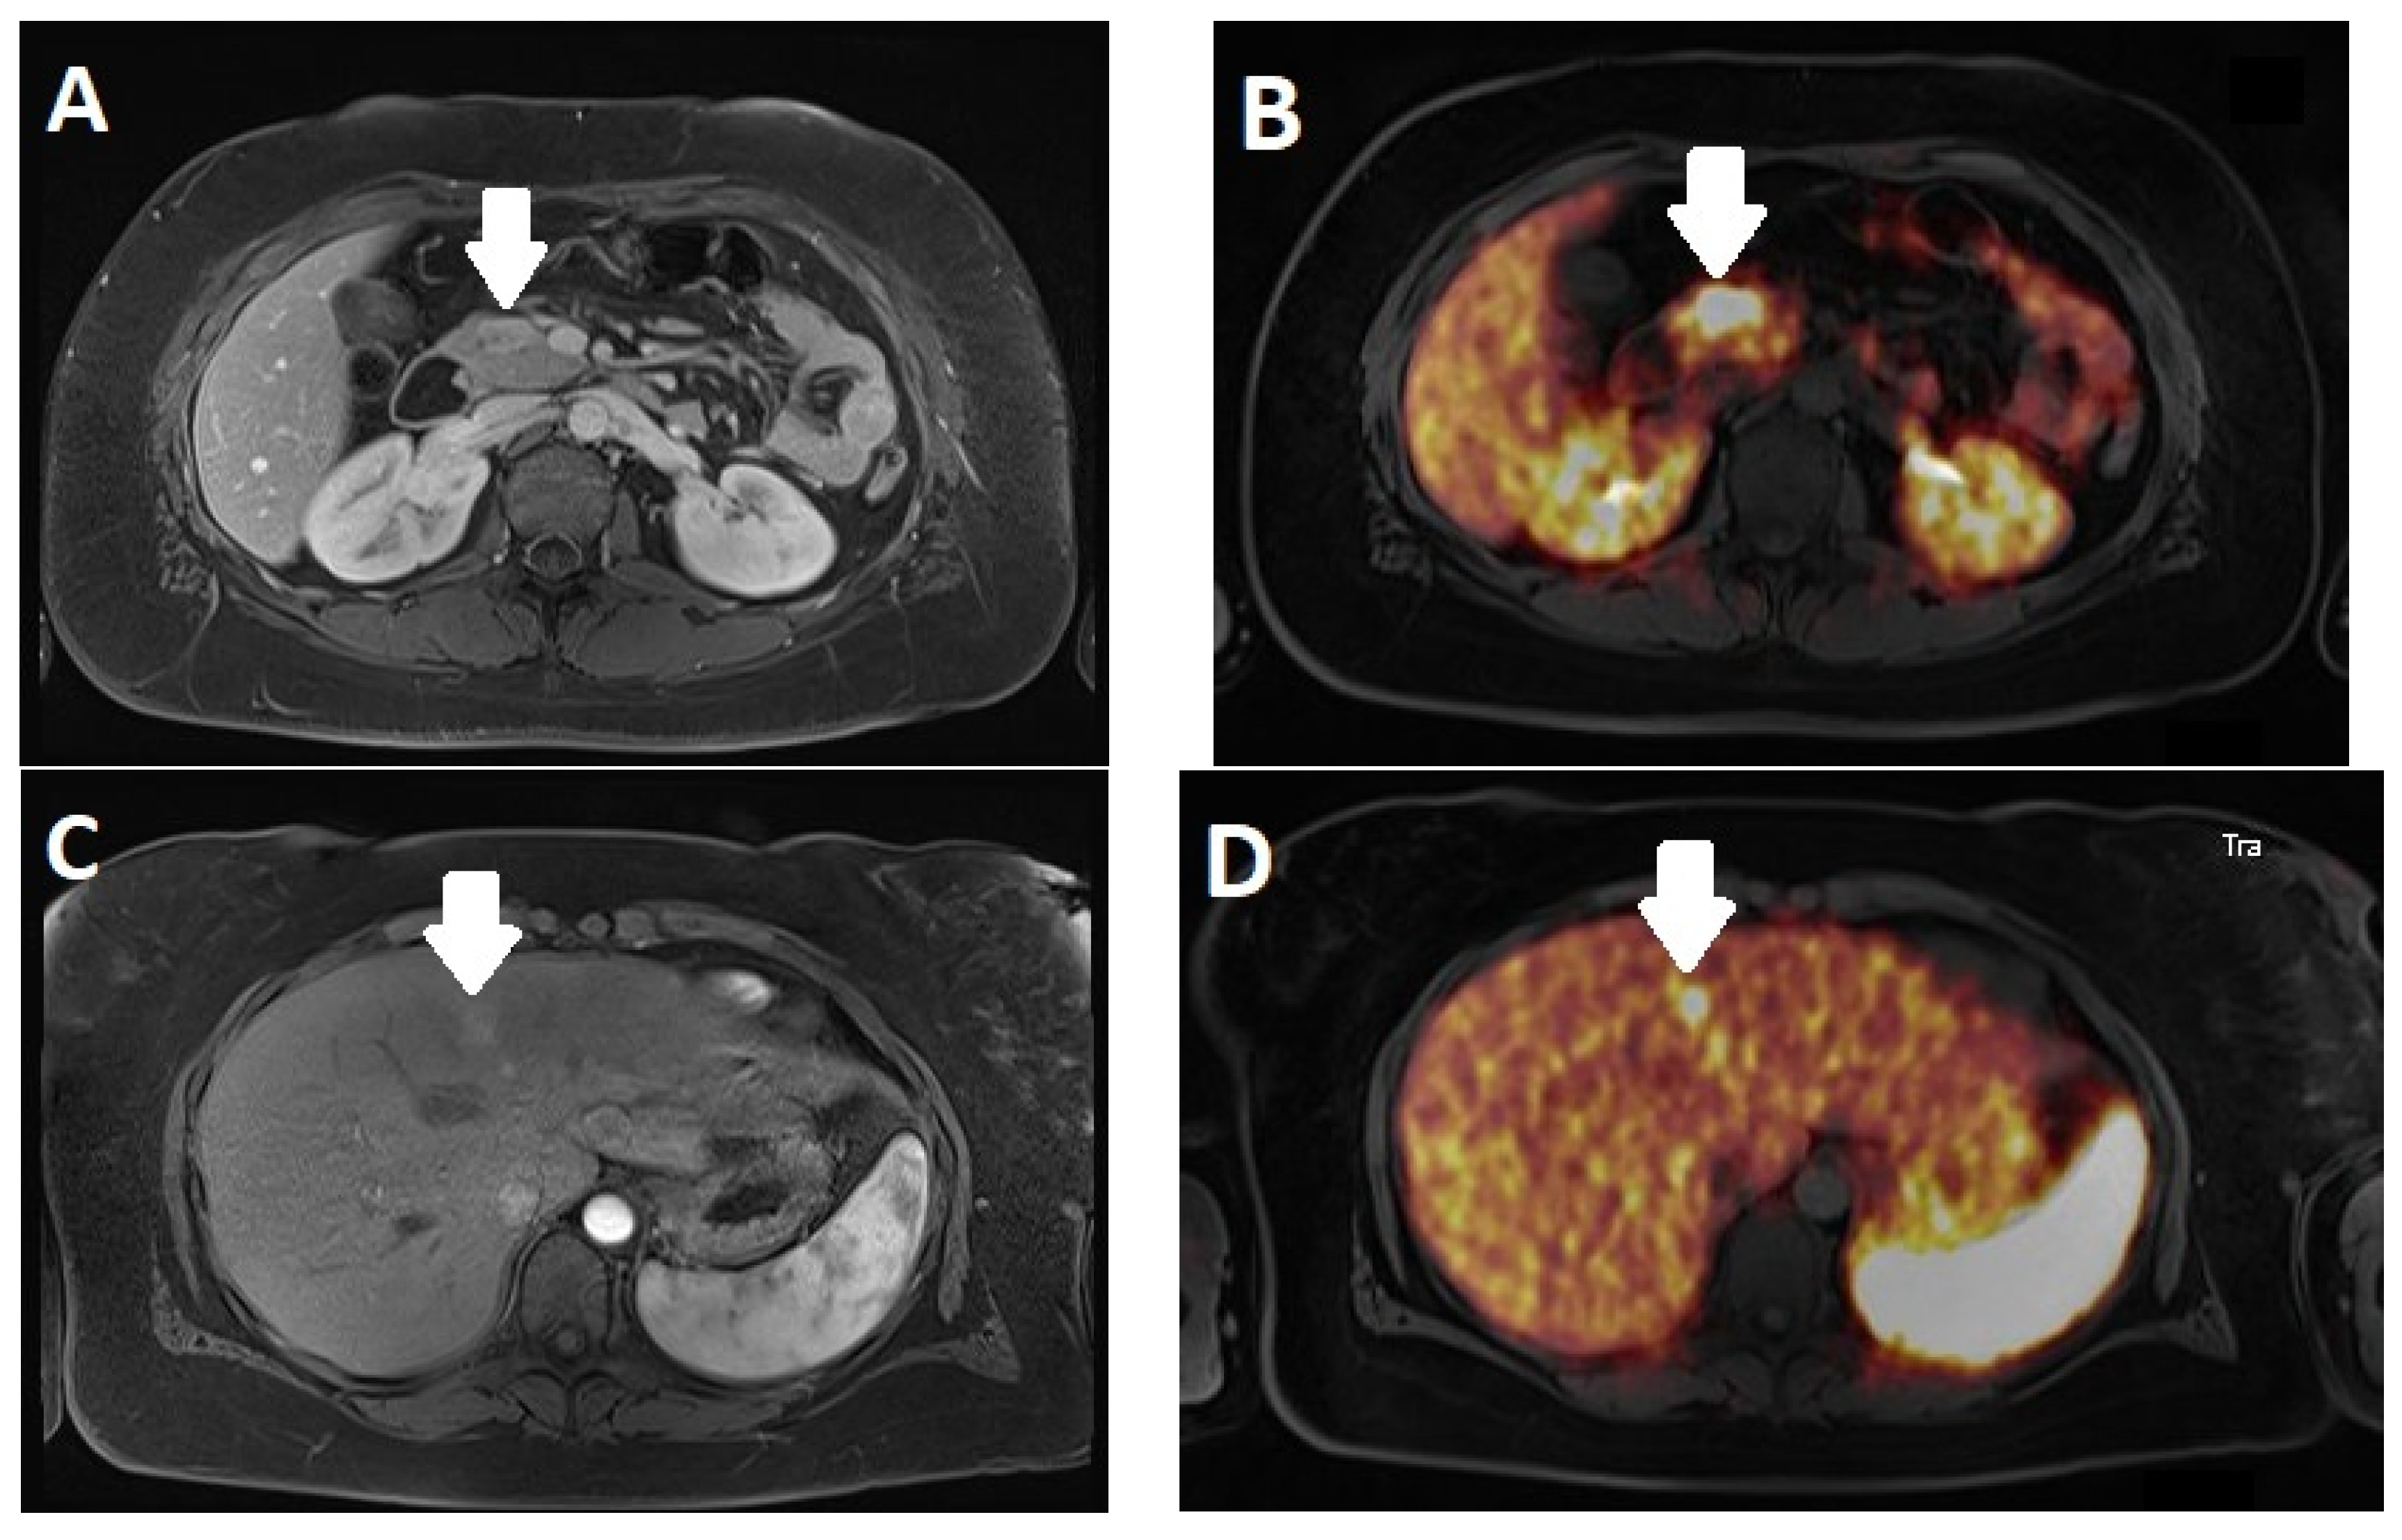

3.4. Imaging

PET/MRI